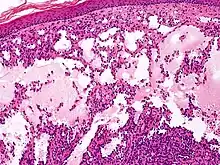

Cavernous lymphangioma, H&E stain. Irregular, dilated spaces are visible in dermis.

Microscopically, the vesicles in lymphangioma circumscriptum are greatly dilated lymph channels that cause the papillary dermis to expand. They may be associated with acanthosis and hyperkeratosis. There are many channels in the upper dermis which often extend to the subcutis (the deeper layer of the dermis, containing mostly fat and connective tissue). The deeper vessels have large calibers with thick walls which contain smooth muscle. The lumen is filled with lymphatic fluid, but often contains red blood cells, lymphocytes, macrophages, and neutrophils. The channels are lined with flat endothelial cells. The interstitium has many lymphoid cells and shows evidence of fibroplasia (the formation of fibrous tissue). Nodules (A small mass of tissue or aggregation of cells) in cavernous lymphangioma are large, irregular channels in the reticular dermis and subcutaneous tissue that are lined by a single layer of endothelial cells. Also an incomplete layer of smooth muscle also lines the walls of these channels. The stroma consists of loose connective tissue with a lot of inflammatory cells. These tumors usually penetrate muscle. Cystic hygroma is indistinguishable from cavernous lymphangiomas on histology.[4]

Composed of dilated lymphatic channels, cavernous lymphangiomas characteristically invade surrounding tissues.